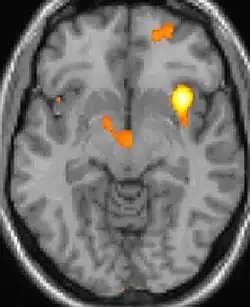

| Diese PET des Gehirns überlagert mit einer Kernspintomographie zeigt eine erhöhte Aktivität in der Schmerzmatrix und im Hypothalamus rechts | ||

Die Positronen-Emissions-Tomographie (PET)-Darstellungen oben zeigen die funktionellen Daten, also die Bereiche, welche bei Schmerzen Aktivität aufweisen, im Vergleich zum Aussehen bei einem schmerzfreien Intervall. Man sieht die sog. Schmerzmatrix, die immer bei Schmerz aktiviert ist und das Areal in der Mitte (in allen drei Ebenen), welches spezifisch im Cluster-Kopfschmerz aktiviert ist. Die VBM Bilder unten zeigen die strukturellen Daten. Hier wird untersucht, ob die Gehirne von Cluster-Kopfschmerz-Patienten anders sind als die Gehirne von Menschen ohne Kopfschmerzen. Nur ein Areal ist anders, da es mehr Graue Substanz enthält: Dieses entspricht dem oben gezeigten funktionellen Areal. Es handelt sich um den Hypothalamus. Dort wird unter anderem der Schlaf-Wach-Rhythmus generiert. Man vermutet daher den Motor des Cluster-Kopfschmerzes im Hypothalamus.[27][28] Mit der 1H-Magnetresonanzspektroskopie konnten auch biochemische Unterschiede zwischen dem Hypothalamus gesunder Menschen und dem Hypothalamus von Cluster-Kopfschmerz-Patienten nachgewiesen werden.[29][30]

Nach Forschungsergebnissen[31] aus dem Oktober 2014 wird aber angenommen, dass die Krankheit eher von einer Netzwerkstörung und nicht nur durch den Hypothalamus verursacht wird. Bei Patienten mit Cluster-Kopfschmerz wurden im Vergleich zu gesunden Individuen Veränderungen der grauen Substanz, in den Bereichen der Schmerzverarbeitung und darüber hinaus, identifiziert. Diese Veränderungen der grauen Substanz unterschieden sich signifikant bei chronischem und episodischem Cluster-Kopfschmerz sowie innerhalb und außerhalb der Episode. Ein Rückgang der grauen Substanz wurde vorwiegend bei chronischem Cluster-Kopfschmerz beobachtet, während episodischer Cluster-Kopfschmerz ein komplexeres und teilweise entgegengesetztes Muster zeigte. Diese Dynamik reflektiert wahrscheinlich die Anpassungsfähigkeit des Gehirns auf wechselnde Reize in Bezug auf kortikale Plastizität und könnte eine Erklärung für die unterschiedlichen Ergebnisse früherer VBM-Studien zu Schmerzen liefern.